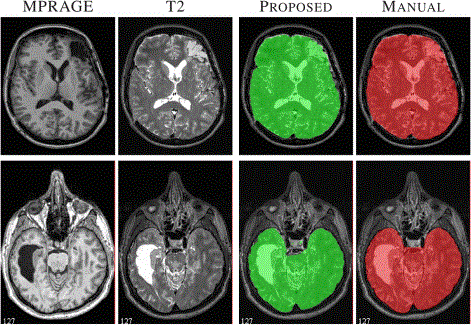

DEMON Deep Multi-Contrast Brain Extraction, Application to Human & Animal Imaging

Description:Human MRI with TBI